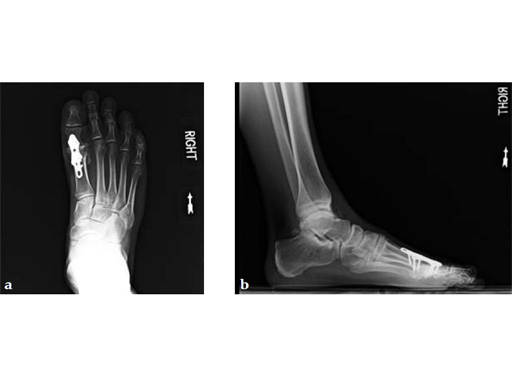

Case 3: First TMT fusion plate

A 48-year-old woman, with hallus valgus and hypermobile medial column, also resulting in pes plano abductovalgus (flatfoot).

Case provided by Andrew Sands, New York, New York, USA

Surgery consisted of first TMT and intertarsal corrective osteotomy plus fusion with movement of the first MT lateral and plantar. This corrects the hallus valgus as well as the PPAV (and stabilizes the medial column).

Case 4: First TMT fusion plate

A 60-year-old woman with pes plano abductovalgus (flatfoot deformity).

The patient was treated by headless compression screw 6.5 tuber osteotomy, TMT plantarflexing osteotomy, and first TMT fusion a plate.